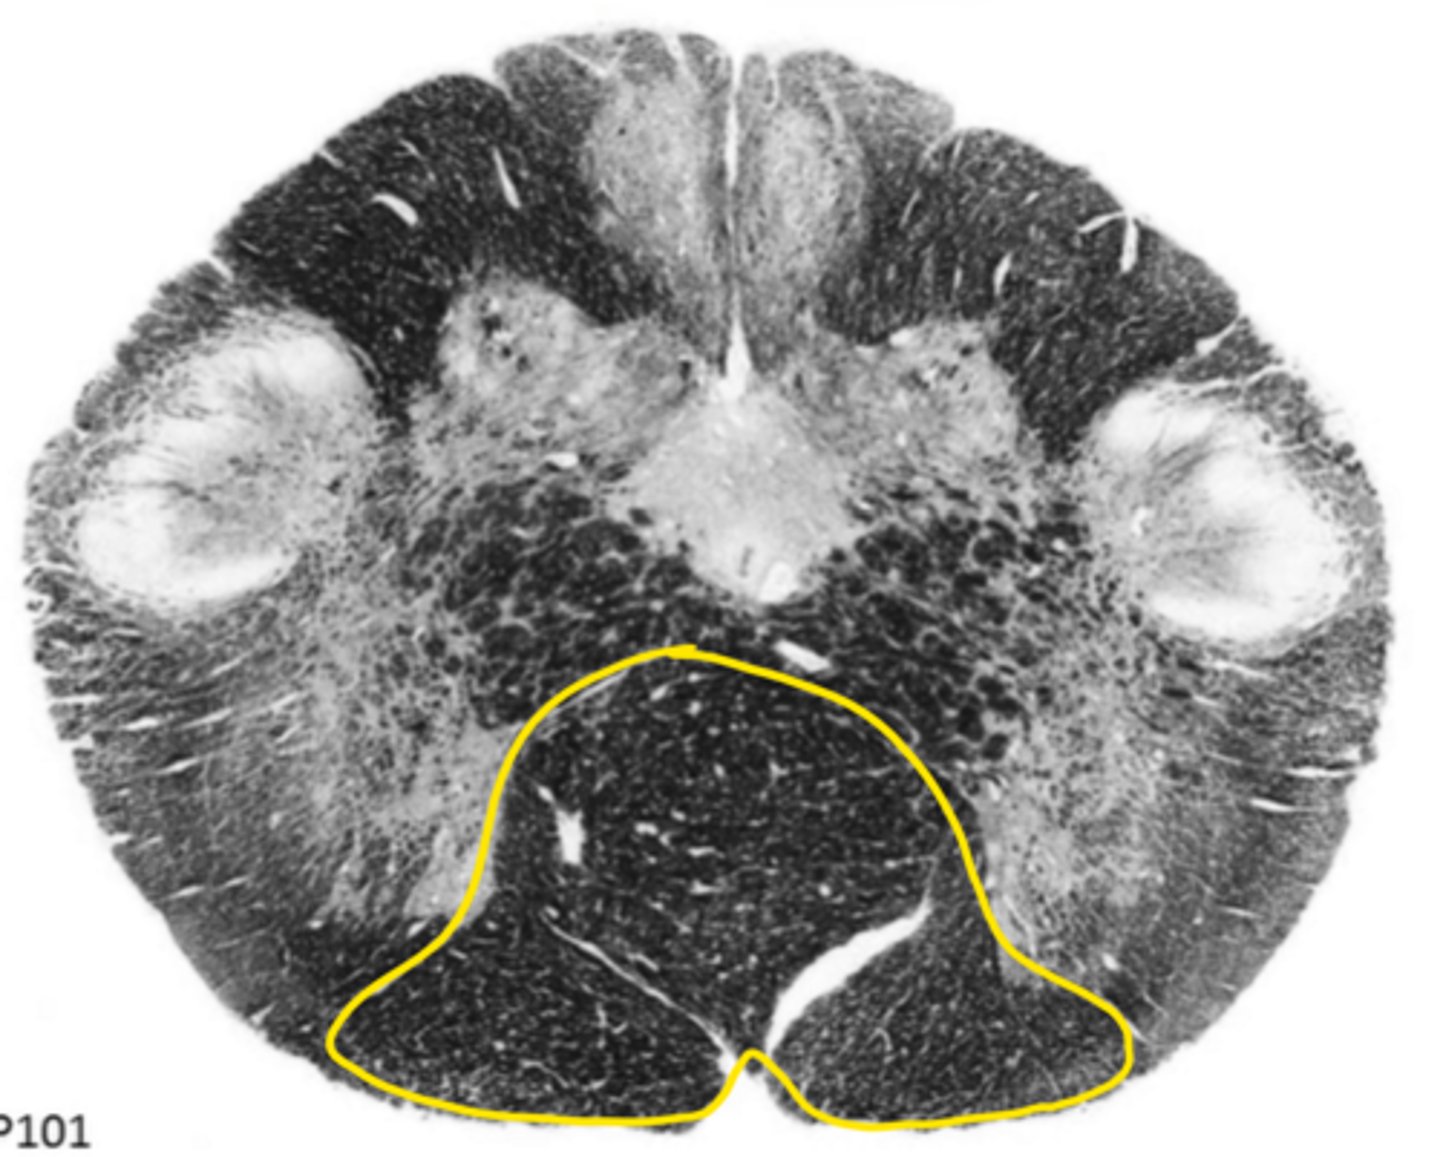

open medulla

ID the brainstem level